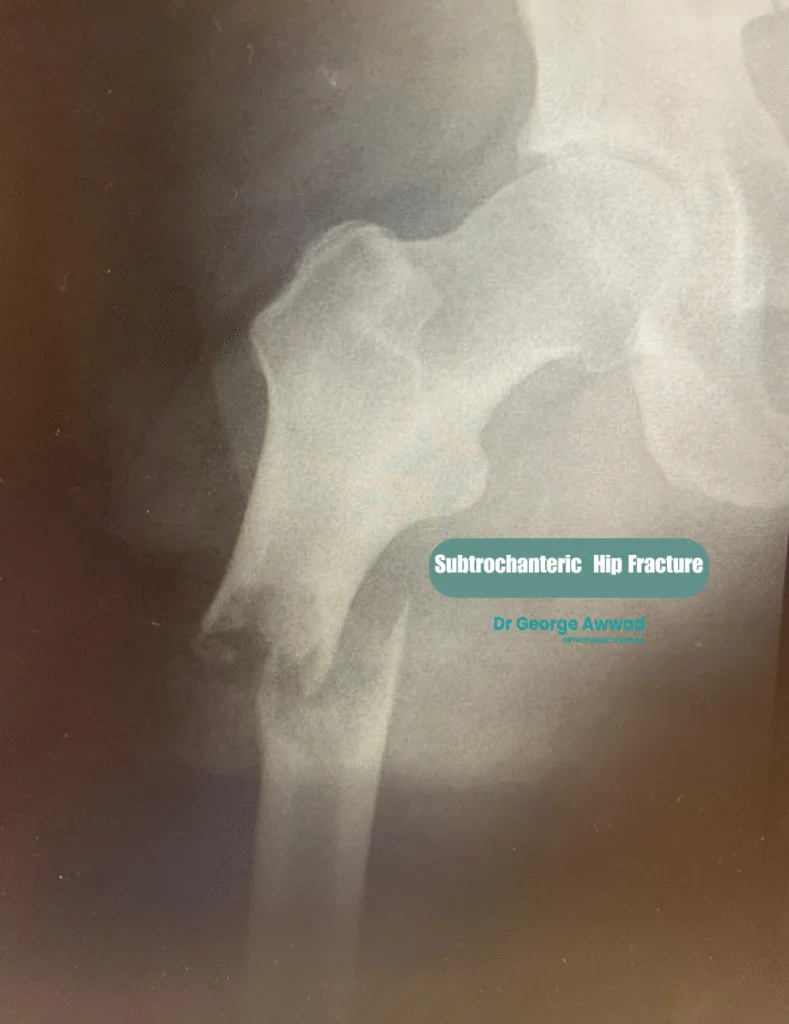

3. Subtrochanteric fractures

These occur in the upper shaft of the femur, just below the lesser trochanter.

Each type of hip fracture presents unique challenges and requires careful assessment to determine the most appropriate surgical approach. These injuries are considered serious, often requiring prompt surgical treatment to restore mobility, reduce pain, and prevent complications such as blood clots, infection, or prolonged immobility. Early intervention is especially important in elderly patients to support their recovery and return to independence. Dr Awwad will review your imaging and clinical status to recommend the best treatment for your specific fracture.